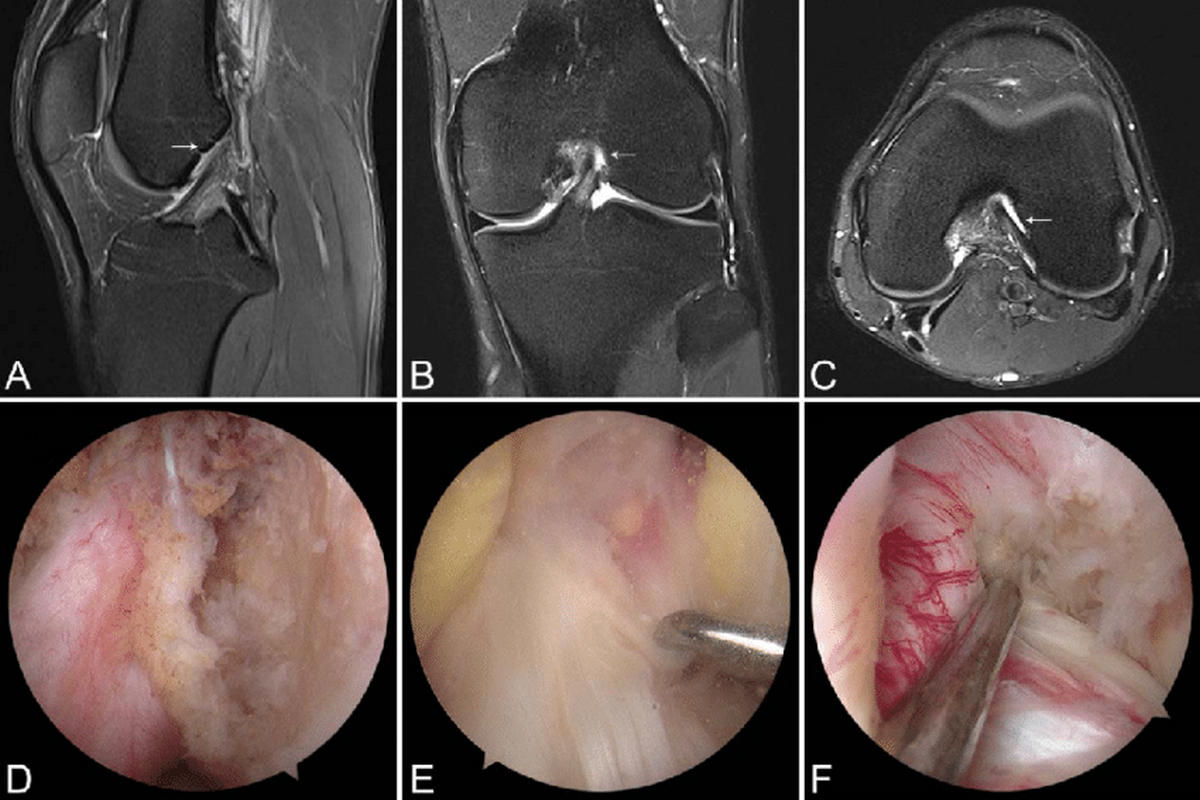

Μαγνητική τομογραφία (MRI), που επιβεβαιώνει τη ρήξη πρόσθιου χιαστού και αναδεικνύει συνοδές βλάβες σε μηνίσκους, χόνδρο ή πλάγιους συνδέσμους

Η MRI αποτελεί την εξέταση εκλογής για την τεκμηρίωση της βλάβης.

Χειρουργική ανακατασκευή πρόσθιου χιαστού

Η αρθροσκοπική ανακατασκευή ΠΧΣ αποτελεί τη θεραπεία εκλογής σε:

Η επέμβαση πραγματοποιείται αρθροσκοπικά με χρήση μοσχεύματος: